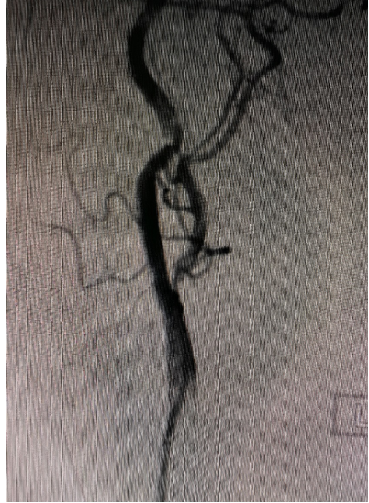

入院影像检查

导丝怎么扩【载药时代 球扩天下】NOVA DES®颅内药物洗脱支架在大脑中动脉重度狭窄中的应用两例!_https://www.jmylbn.com_新闻资讯_第16张

导丝怎么扩【载药时代 球扩天下】NOVA DES®颅内药物洗脱支架在大脑中动脉重度狭窄中的应用两例!_https://www.jmylbn.com_新闻资讯_第17张

重要影像结论DSA:左侧大脑中动脉M1段重度狭窄。